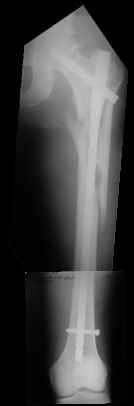

I would use a small wire distractor mentioned in the list some times. Proximal wire is in the iliac crest in AP direction. The leg is adducted. I attached some images. At the AP view under image intensifier you can see adduction but even slight valgus reduction.